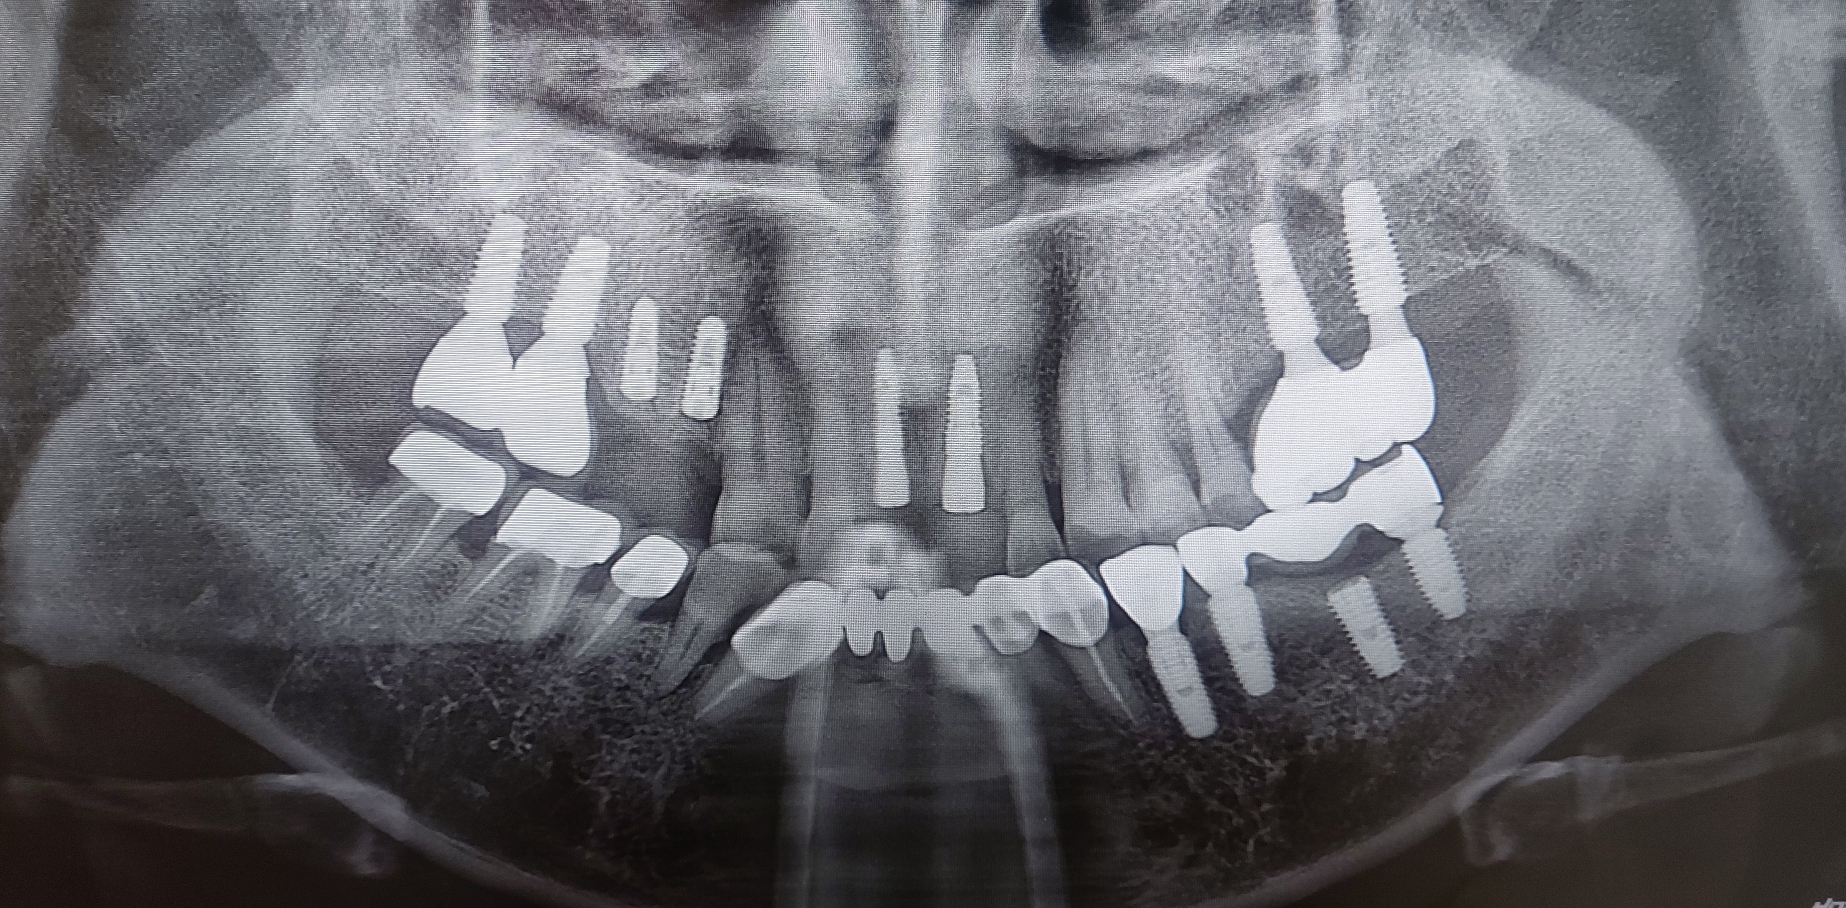

치아 뿌리에 우식이 있는 환자분이 과자봉지를 치아로 뜯다고 앞니 치아가 부러진것을 주소로 내원하셨습니다. 환자분 굉장히 당황해 하셨고 최대한 빨리 치아를 올려 드리기로 결정한 환자분입니다.

가장 중요한 부분은 atraumatic extraction 즉 외상이 거의 가지 않는 발치입니다. 저도 최대한 조심스럽게 발치할려고 노력하였지만 워낙 치아가 뼈와 유착이 되어 있어서 발치시 애를 많이 먹었습니다.

발치를 시행하고 UV임플란트를 식립하였습니다. 그리고 빈공간에 인공뼈를 이식후 봉합 시행하고 바로 구강스캐너를 이용하여 인상채득을 시행하였습니다. 수술 날짜가 3월 20일 오후경이고 오늘 3월 22일 치아를 넣어 드렸습니다.